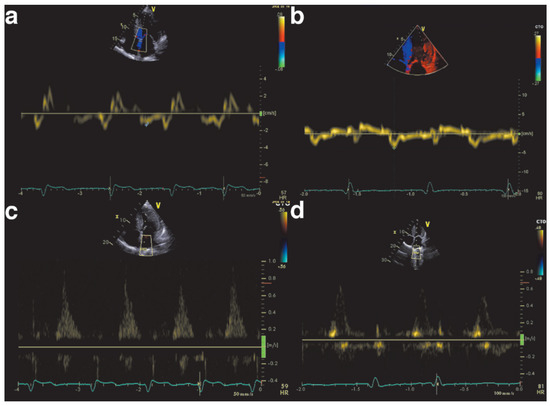

Echocardiography is key in detecting cardiac involvement in amyloidosis. Ohen, a hypertrophic cardiomyopathy is initially suspected on the basis of increased wall thickness and low ventricular volume (Figure 2). Tissue Doppler and strain measurements are especially important to detect diastolic and systolic dysfunction as patients initially present with HFpEF. The ventricle will first show diastolic dysfunction (Figure 3) due to noncom-pliance of the infiltrated myocardium, and in more advanced stages systolic dysfunction. Cardiac amyloidosis is characterised by regional variations in longitudinal strain, typically with apical sparing (Figure 4). Also a “granular sparkling appearance” of the leh ventricle is typical (important: switch off second harmonic imaging, as it may produce sparkling appearance in non-amyloidosis patients). Doppler measurements show restrictive filling patterns with increased leh ventricular filling pressures. Additionally the aortic and mitral valves appear thickened (amyloid deposits), as well as the intra-atrial septum and the right ventricle. The atria are typically dilated and quite ohen a pericardial effusion is found. The combination of echocardiographic signs of hypertrophic cardiomyopathy and a normal or low voltage ECG have a high sensitivity and specificity for amyloidosis [9,10,11].

Figure 2. Echocardiographic example of hypertrophic cardiomyopathy caused by amyloidosis.

Figure 3. Echocardiographic example of diastolic dysfunction in amyloidosis. Panels a and b show low septal and lateral tissue Doppler e’ values, characteristic of high left ventricular end diastolic pressure. Panels c and d show decreased pulmonary vein systolic flow, and increased diastolic flow.